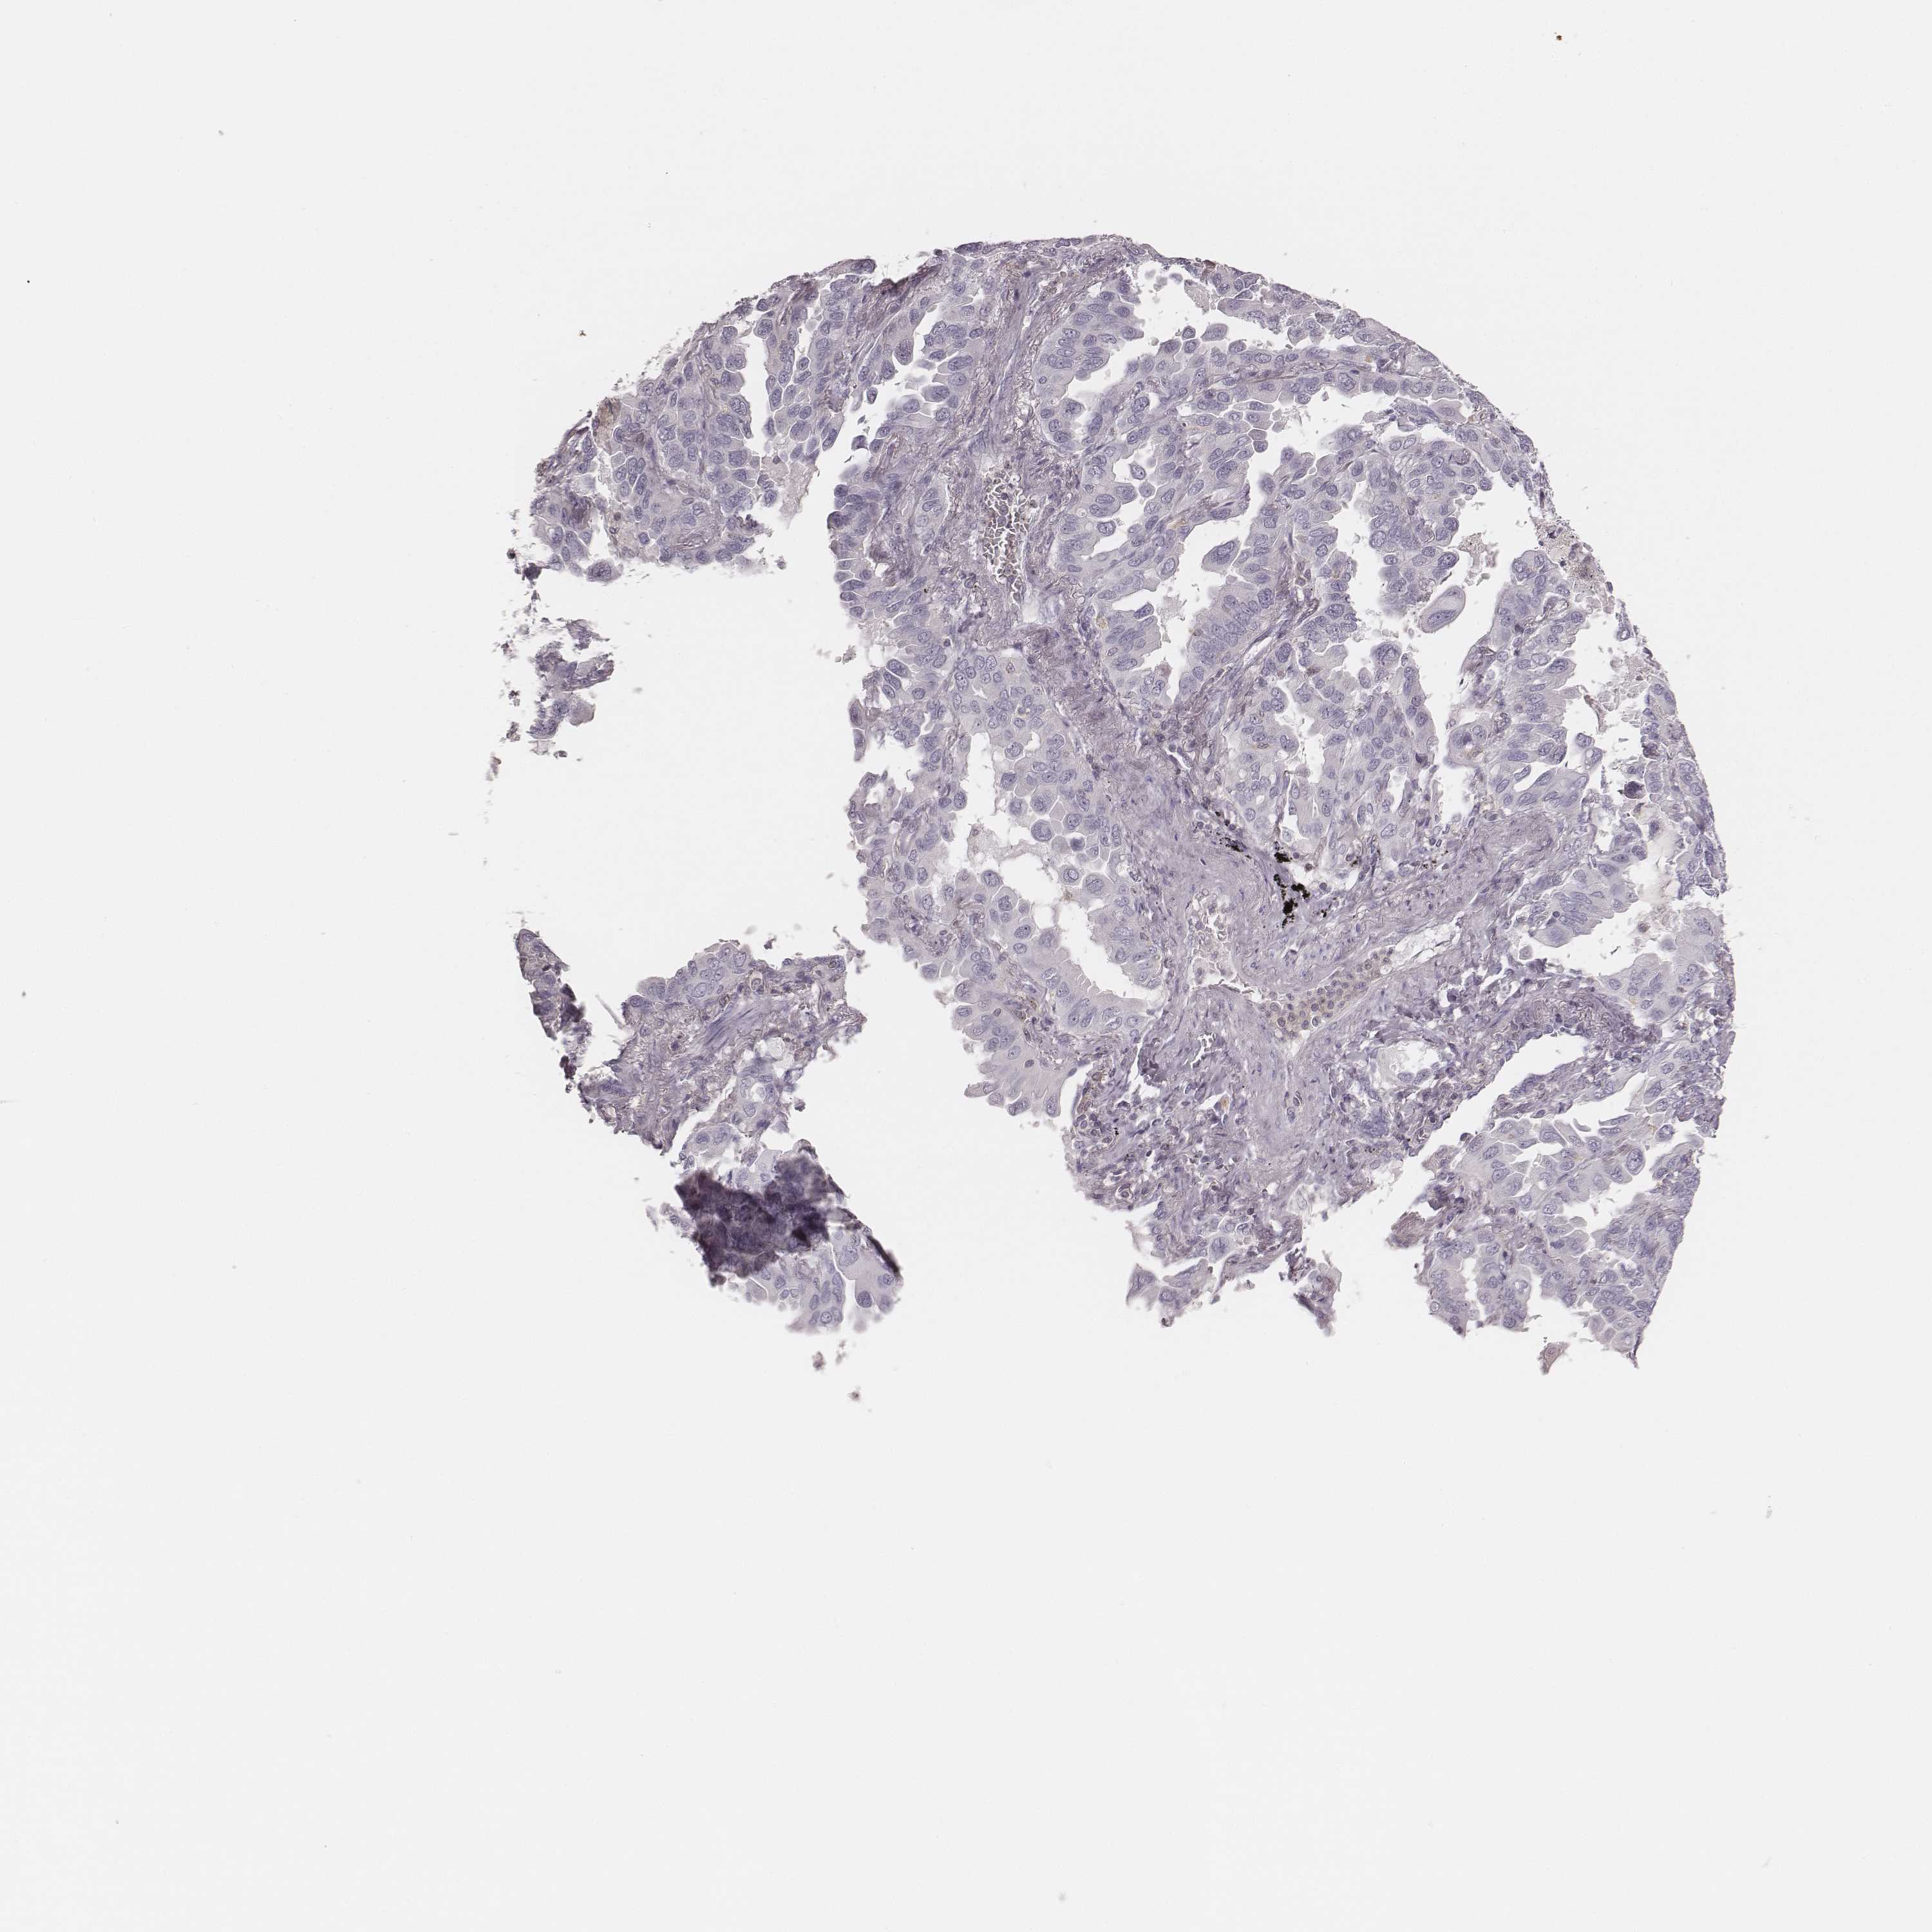

CANCER LUNG CANCER Show tissue menu

Lung cancer

Human cancer